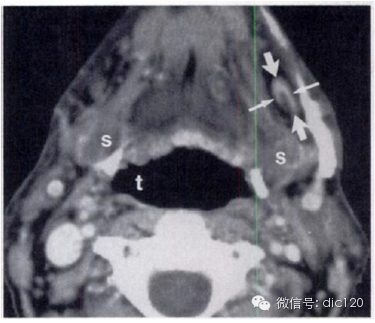

Ⅴ区 包括颈后三角淋巴结群。这一淋巴结群包括沿脊副神经下部和颈横血管的淋巴结。 Ⅴ区上界为胸锁乳突肌止点处和斜方肌,下界为锁骨, 从影像学角度采用舌骨体上缘作为Ⅴ区的上界 ,前以胸锁乳突肌后缘为界,后以斜方肌前侧缘为界。Ⅴ区接受来自枕骨和耳后淋巴结的淋巴管,来自枕骨和顶骨头皮、侧颈和后颈皮肤及肩部、鼻咽和口咽(扁桃体和舌根) 的淋巴管,是鼻咽、口咽、声门下喉、梨状窝顶、颈段食管和甲状腺肿瘤发生隐匿性转移的高危区

![]()